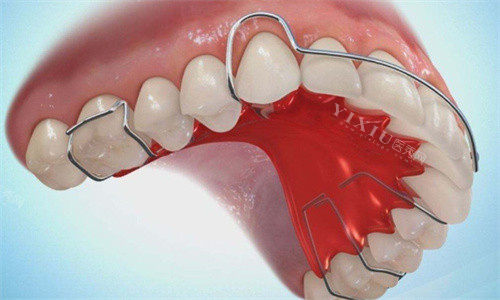

在牙齿矫正的旅途中,佩戴保持器是至关重要的一环,它如同守护牙齿新排列秩序的“卫士”,确保矫正成果得以稳固。然而,由于种种原因,部分患者可能会在矫正结束后的一段时间内忽视或忘记佩戴保持器,这不禁让人担忧:长时间没有戴保持器,牙齿会发生什么变化?如果现在强行戴上,是否还能有效?针对这些疑问,我们特邀牙科医生,为您详细解答。

4.强行戴上不一定有用

面对长时间未戴保持器后牙齿的变化,部分患者可能会尝试强行戴上原来的保持器,希望能将牙齿“掰”回原样。然而,这种做法往往收效甚微,甚至可能带来伤害。

5.牙齿适应性差

长时间未佩戴保持器,牙齿已经适应了新的位置和环境。此时,强行戴上原本的保持器,可能会因为牙齿位置的改变而导致不适甚至疼痛。此外,保持器的形状和尺寸也可能因长时间未使用而发生变化,不再适合当前的牙齿状况。

6.牙周组织受损